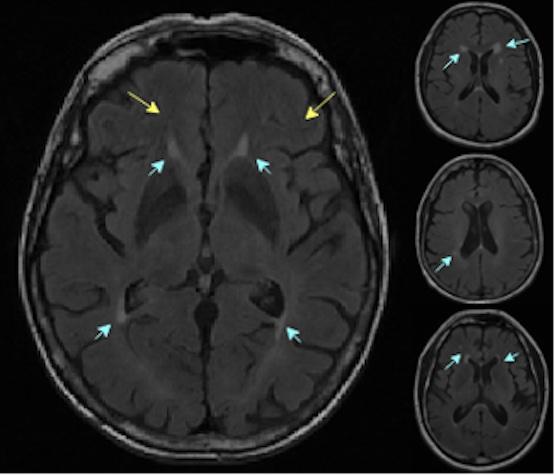

Automated identification of white matter hyperintensities on MR imaging.